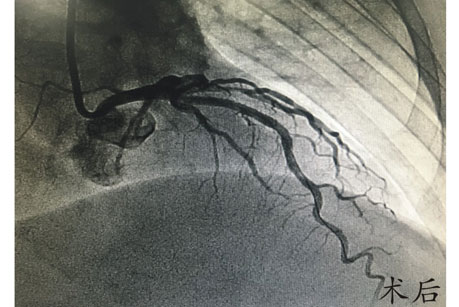

在赵慧强主任的指导下,心内科介入治疗团队选择创伤最小的桡动脉径路,应用常规穿刺器械及造影导管完成了对患者的冠脉造影检查,造影提示患者前降支近段90%节段性重度狭窄,根据患者病变情况,必须行冠脉介入治疗置入支架。经介入团队讨论后,决定即刻对患者进行前降支介入治疗,考虑患者体型小,主动脉窦部较窄,在没有专用指引导管的情况下,选用常规较小型号指引导管顺利到达左冠开口,随后应用常规导丝顺畅通过病变部位,球囊预扩张及支架置入先后顺利完成,全程仅耗时40分钟,手术取得圆满成功。